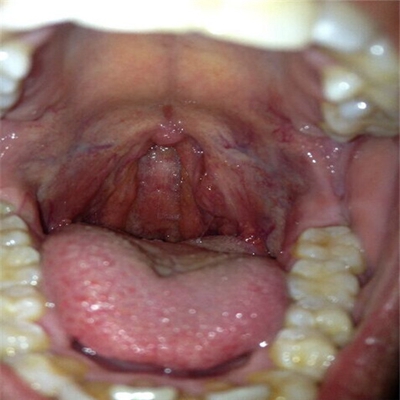

扁桃體惡性腫瘤圖片

扁桃體癌圖 (9)